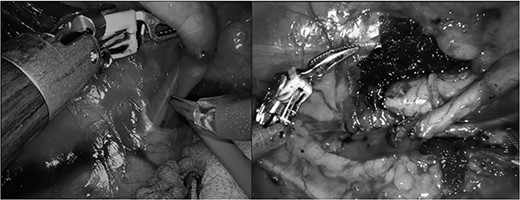

We report a case of a 60-years-old female, who came to our attention for persistent right flank pain and urinary tract infection. The computed tomography (CT) scan revealed right hydronephrosis with dilatation of the upper third of the ureter, up to L4, where it curved posteriorly to the IVC passing to its medial then anterior surface (Fig. 1). The 99mTc mercaptoacetyltriglycine (MAG-3) renal scan showed an obstructed pattern. After obtaining the patient’s consent, a robotic correction of the RCU was planned with the Da Vinci Xi. The patient was placed in lateral position. A pneumoperitoneum was created using a Veress needle, and the four robotic ports, spaced ⁓6 cm apart, were placed in a linear fashion on midclavicular line. Two ports for the assistant were placed at the lateral border of the rectus muscle. After the mobilization of the right colon to expose the retroperitoneal space, the ureter, the gonadic vain, the IVC and the renal pelvis were identified. After the transection of the ureter 3 cm below the ureteropelvic junction, the retrocaval segment was transposed anteriorly to the IVC and an ureteroureterostomy was performed with interrupted 4–0 monofilament sutures. After completion of the posterior layer, a 6F double J stent was insert in a retrograde fashion and the anastomosis was completed (Fig. 2). The operative time was 140 min, of which 90 min of console time. The post-operative stay was regular, the patient was discharged on post-operative day 4. The double J stent was removed after 30 post-operative days. After 1 year of follow-up the patient remains asymptomatic and imaging showed no signs of obstruction.

Intraoperative images of the ureter behind the IVC and after the transposition and the ureteroureterostomy.